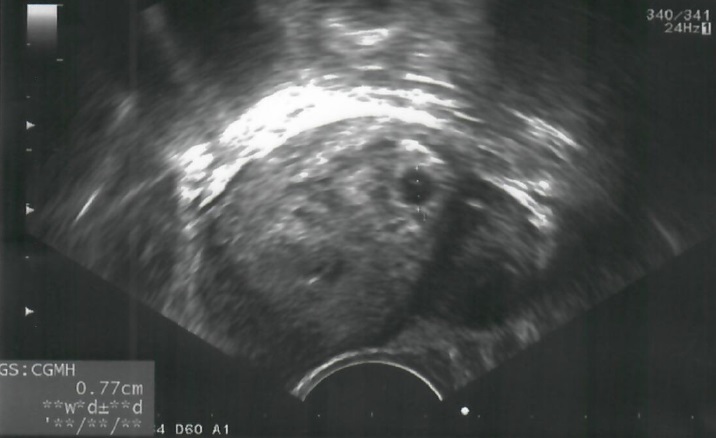

茂盛醫院在7/20出現了第一位申請試管補助且順利懷孕的婦女,30歲的黃太太因為輸卵管阻塞而不孕,於是今年初至本院接受林秉瑤醫師的試管療程,並已接受2次的取卵手術,共培育9顆胚胎。期間,聽聞政府將推行試管補助方案,內心非常期待。黃太太說:「當林秉瑤醫師通知我們去申請試管補助方案時,我們立刻趕在第2天提出申請,爾後植入1顆健康胚胎,更驚喜能在方案上路的短短20天就受孕了,這是我收過最棒的生日禮物,好感謝林醫師,還有政府推出這個德政!」黃先生也說,年紀輕時想先打拼工作再談婚姻,如果這個補助方案能早幾年推出,可減輕經濟負擔,肯定會提早結婚生子!